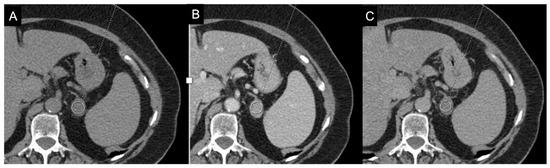

More specifically, the study by Andersen et al. focused on adrenal metastases from lung cancer [101]. They found several texture parameters statistically significantly in differentiating metastatic and benign adrenal lesions in patients with lung cancer (Figure 15).

Figure 15.

Segmentation of the metastatic lesion (arrow) of the left adrenal gland (same patient of Figure 4) on venous phase CT, using 3D-Slicer Software, version 4.11.